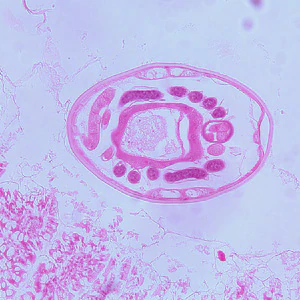

A four-year-old child was admitted to the hospital for sever abdominal pain mimicking appendicitis. A small section of bowel was removed and sent to the Pathology Department for work-up. A section of tissue was preserved in formalin, sectioned, and stained with hematoxylin and eosin (H&E). Images A–C show what was observed at 100x magnification of slides made from the tissue specimen. In addition to the biopsy, stool was collected for routine ova and parasite (O&P) examination. The object is Figure D, which measured on average 73 micrometers long by 37 micrometers wide, was seen in low numbers in a concentrated wet mount from a formalin-preserved aliquot of the stool. What is your diagnosis? Based on what criteria?

Figure D